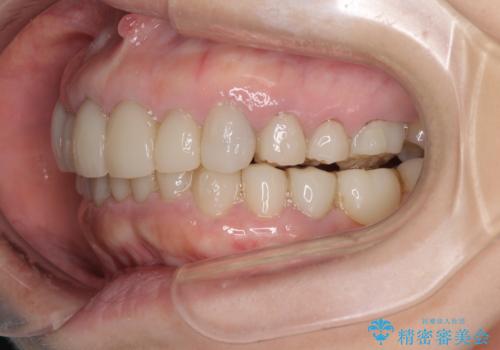

- 下顎の前歯に激痛を覚えて来院された患者様です。

取り急ぎ下顎前歯数歯の根管治療を、銀座しらゆり歯科医院長の林先生にお願いし、それ以外に気になっている、不自然な色調のクラウン、金属部分が見えてブラッシングがしにくいインプラント補綴、口元の突出感、出血のしやすい歯周ポケットなど、全てを解決するための治療を行うこととしました。